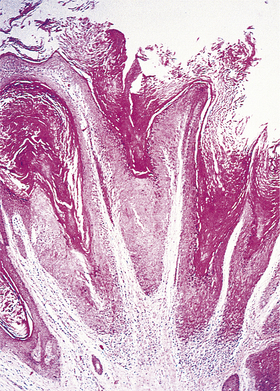

Solid tumours consist of neoplastic cells and stroma (see below and Fig. 11.3). The neoplastic cells reproduce to a variable extent the growth pattern and synthetic activity of the parent cell of origin. Depending on their functional resemblance to the parent tissue, they continue to synthesise and secrete cell products such as collagen, mucin or keratin; these often accumulate within the tumour where they are recognisable histologically. Other cell products may be secreted into the blood where they can be used clinically to monitor tumour growth and the effects of therapy (p. 234).

image

Fig. 11.3 Tumour cells and stroma. Histology of an epithelial neoplasm showing the darkly staining tumour cells embedded in a paler connective tissue stroma.